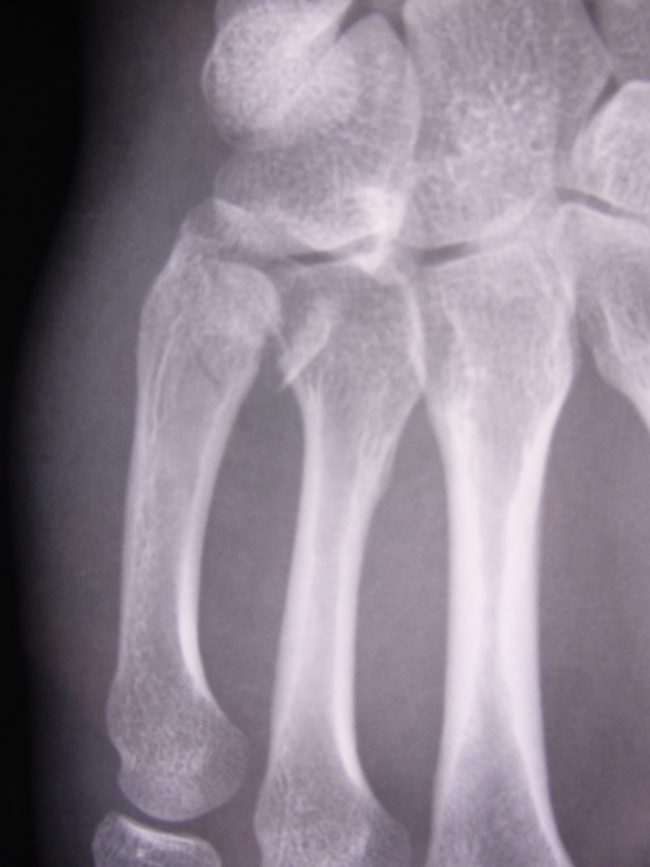

La fracture passe souvent inaperçue par l’examen de la main aux urgences et seule la radiographie et le scanner peuvent faire le diagnostic.

Il est important de préciser combien de métacarpiens sont atteints et s’il s’agit de fractures simples, fractures articulaires ou fractures luxations.

Les radiographies ne suffisent pas à un diagnostic précis.

Seul le scanner permet un examen détaillé.